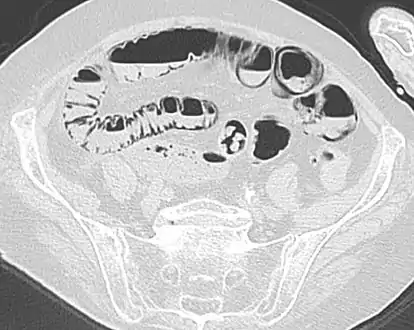

- Pneumatosis intestinalis at computed tomography in intestinal ischemia. Lung window for better representation of the gas deposits in the intestinal walls. Coronal reconstruction.